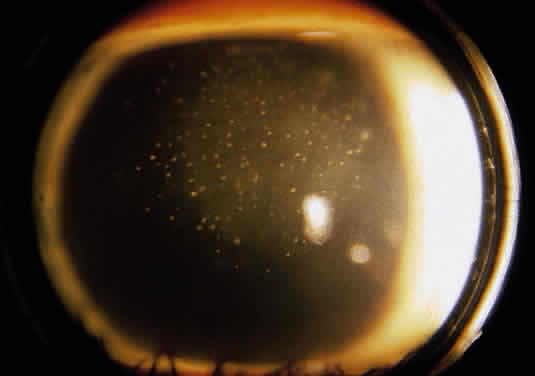

Recurrent disease most often affects the cornea, and can affect any or all layers. The characteristic epithelial lesions are dendrites: thin, meandering, arborizing epithelial ulcerations, sometimes with terminal bulbs at the ends of fine branches. Stromal disease may be immune or infectious, or invoke combined mechanisms. The commonly described patterns of stromal herpetic disease include disciform edema, necrotizing stromal keratitis, and immune ring formation. In disciform edema, the dominant feature is disk-shaped stromal edema, without neovascularization or necrosis, that can be focal in milder disease but extensive and diffuse in more severe disease. Folds in Descemet's membrane may accompany corneal thickening, and keratic precipitates accumulate under the area of edema (Fig. 1). Necrotizing stromal keratitis is characterized by inflammatory necrosis and infiltration of the cornea with polymorphonuclear leukocytes, macrophages, lymphocytes, and plasma cells.7 This cellular infiltration produces stromal edema and necrosis. The necrotizing focus can be located at any level of the corneal stroma, with or without epithelial ulcer ation. Ring infiltrates often develop. In some cases, diffuse patches of infiltration appear beneath an intact epithelium, followed by local neovascularization; this is the so-called interstitial keratitis pattern. Lipid deposition, stromal melting, descemetocele formation, and perforation are all potential complications of advanced necrotizing stromal keratitis. If the peripheral cornea is involved, inflammation and necrosis can spread to the sclera, producing a sclerokeratitis.